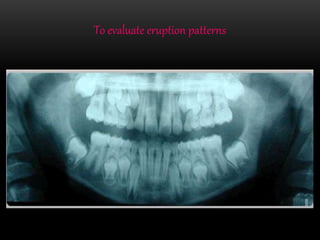

To evaluate eruption patterns

To detect diseases, lesions, conditions of the jaws

and the extent of large lesions.

to evaluate trauma

Retainedteethor root tips in edentulous patients

Post-operative examination and patient education.

Implants